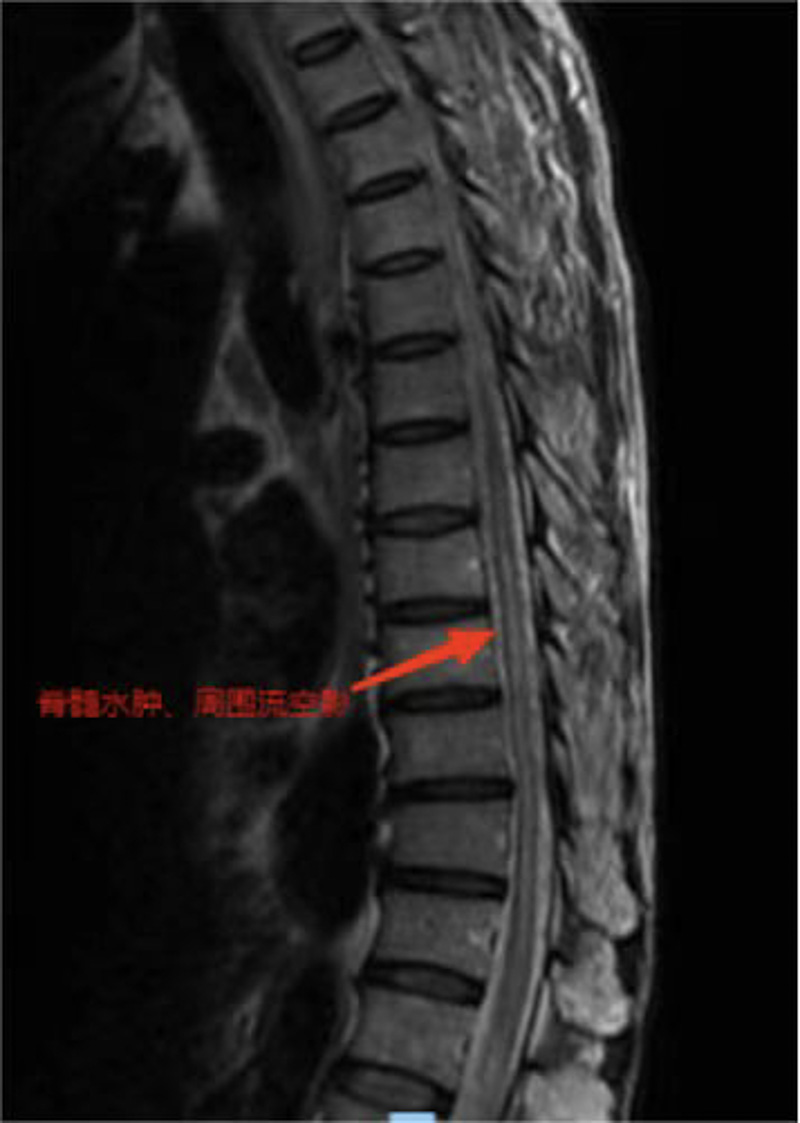

方先生(化名)年過六旬,身體硬朗,但是近一年來逐漸出現了下肢乏力,一開始只是不愿多走路,半年前,乏力癥狀已經影響到了正常生活,這才引起了他的重視。此前雖然方先生輾轉就醫,卻始終無法得到明確的診斷,抱著最后一線希望,他于日前來到了柳州市人民醫院神經外科就診。醫生很快在患者磁共振檢查結果中找到了關鍵線索——方先生脊髓血管有異常,考慮下肢乏力與此有關。經過詳細的檢查和分析,神經外科團隊診斷方先生患的是胸椎硬脊膜動靜脈瘺。

救治刻不容緩,醫院立即組織神經外科、神經內科及麻醉科等開展多學科會診,結合方先生的情況綜合判斷,為他設計了治療方案,經胸髓CTA、血管造影,明確瘺口在胸10椎體水平,決定實施顯微鏡小切口半椎板入路手術切除瘺口。

術后經過醫護團隊細心的治療護理,復查磁共振胸髓水腫消失,患者雙下肢感覺及乏力癥狀明顯改善。